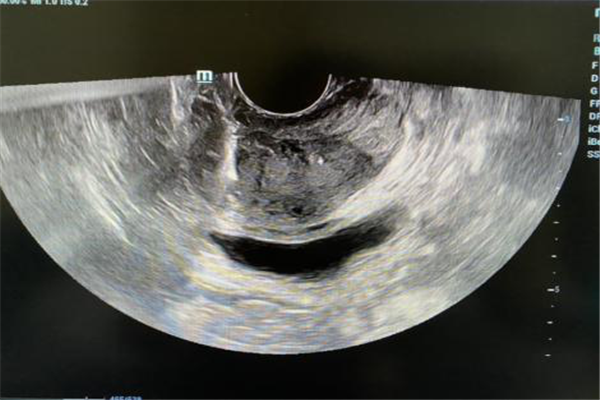

如何早期診斷前列腺癌至關(guān)重要。前列腺癌可以表現(xiàn)為排尿困難、尿頻、尿流弱或中斷,無(wú)法站立排尿,直腸有壓迫感或疼痛等等,與前列腺炎和前列腺增生相似?,F(xiàn)階段隨著醫(yī)療技術(shù)的發(fā)展和水平的提高,超聲引導(dǎo)下經(jīng)直腸前列腺穿刺活檢技術(shù)的應(yīng)用,對(duì)疑似的患者進(jìn)行穿刺病理診斷已經(jīng)成為前列腺癌的主要診斷方法。

超聲引導(dǎo)下經(jīng)直腸前列腺穿刺活檢術(shù),由于安全簡(jiǎn)便、穿刺準(zhǔn)確性和成功率高,在臨床上已廣泛應(yīng)用。自2020年8月起,我院超聲醫(yī)學(xué)科底已經(jīng)成功穿刺15例,陽(yáng)性率高,為前列腺分級(jí)、分期提供病理依據(jù)及臨床選擇治療方案提供重要參考。